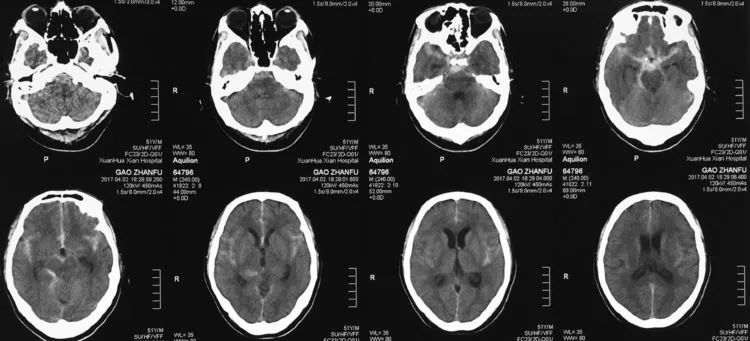

例1,男,50岁,因突发头痛伴恶心、呕吐12小时于2017年4月3日收入院。查体:颈强三横指,余无阳性体征。头颅CT(2017年4月2日)示SAH: